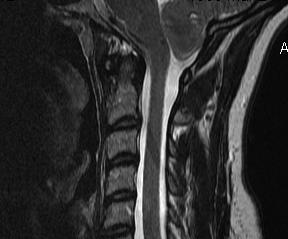

MRI

Most sensitive investigation

- main differential is oedema

- need T1 image

Look for obstructions

- ACM

- spinal cord tumours

Most common in lower C Spine

- may progressively extend up to medulla & down to lumbar

- fluid-filled tubular cavity

- separate from but usually communicating with central canal